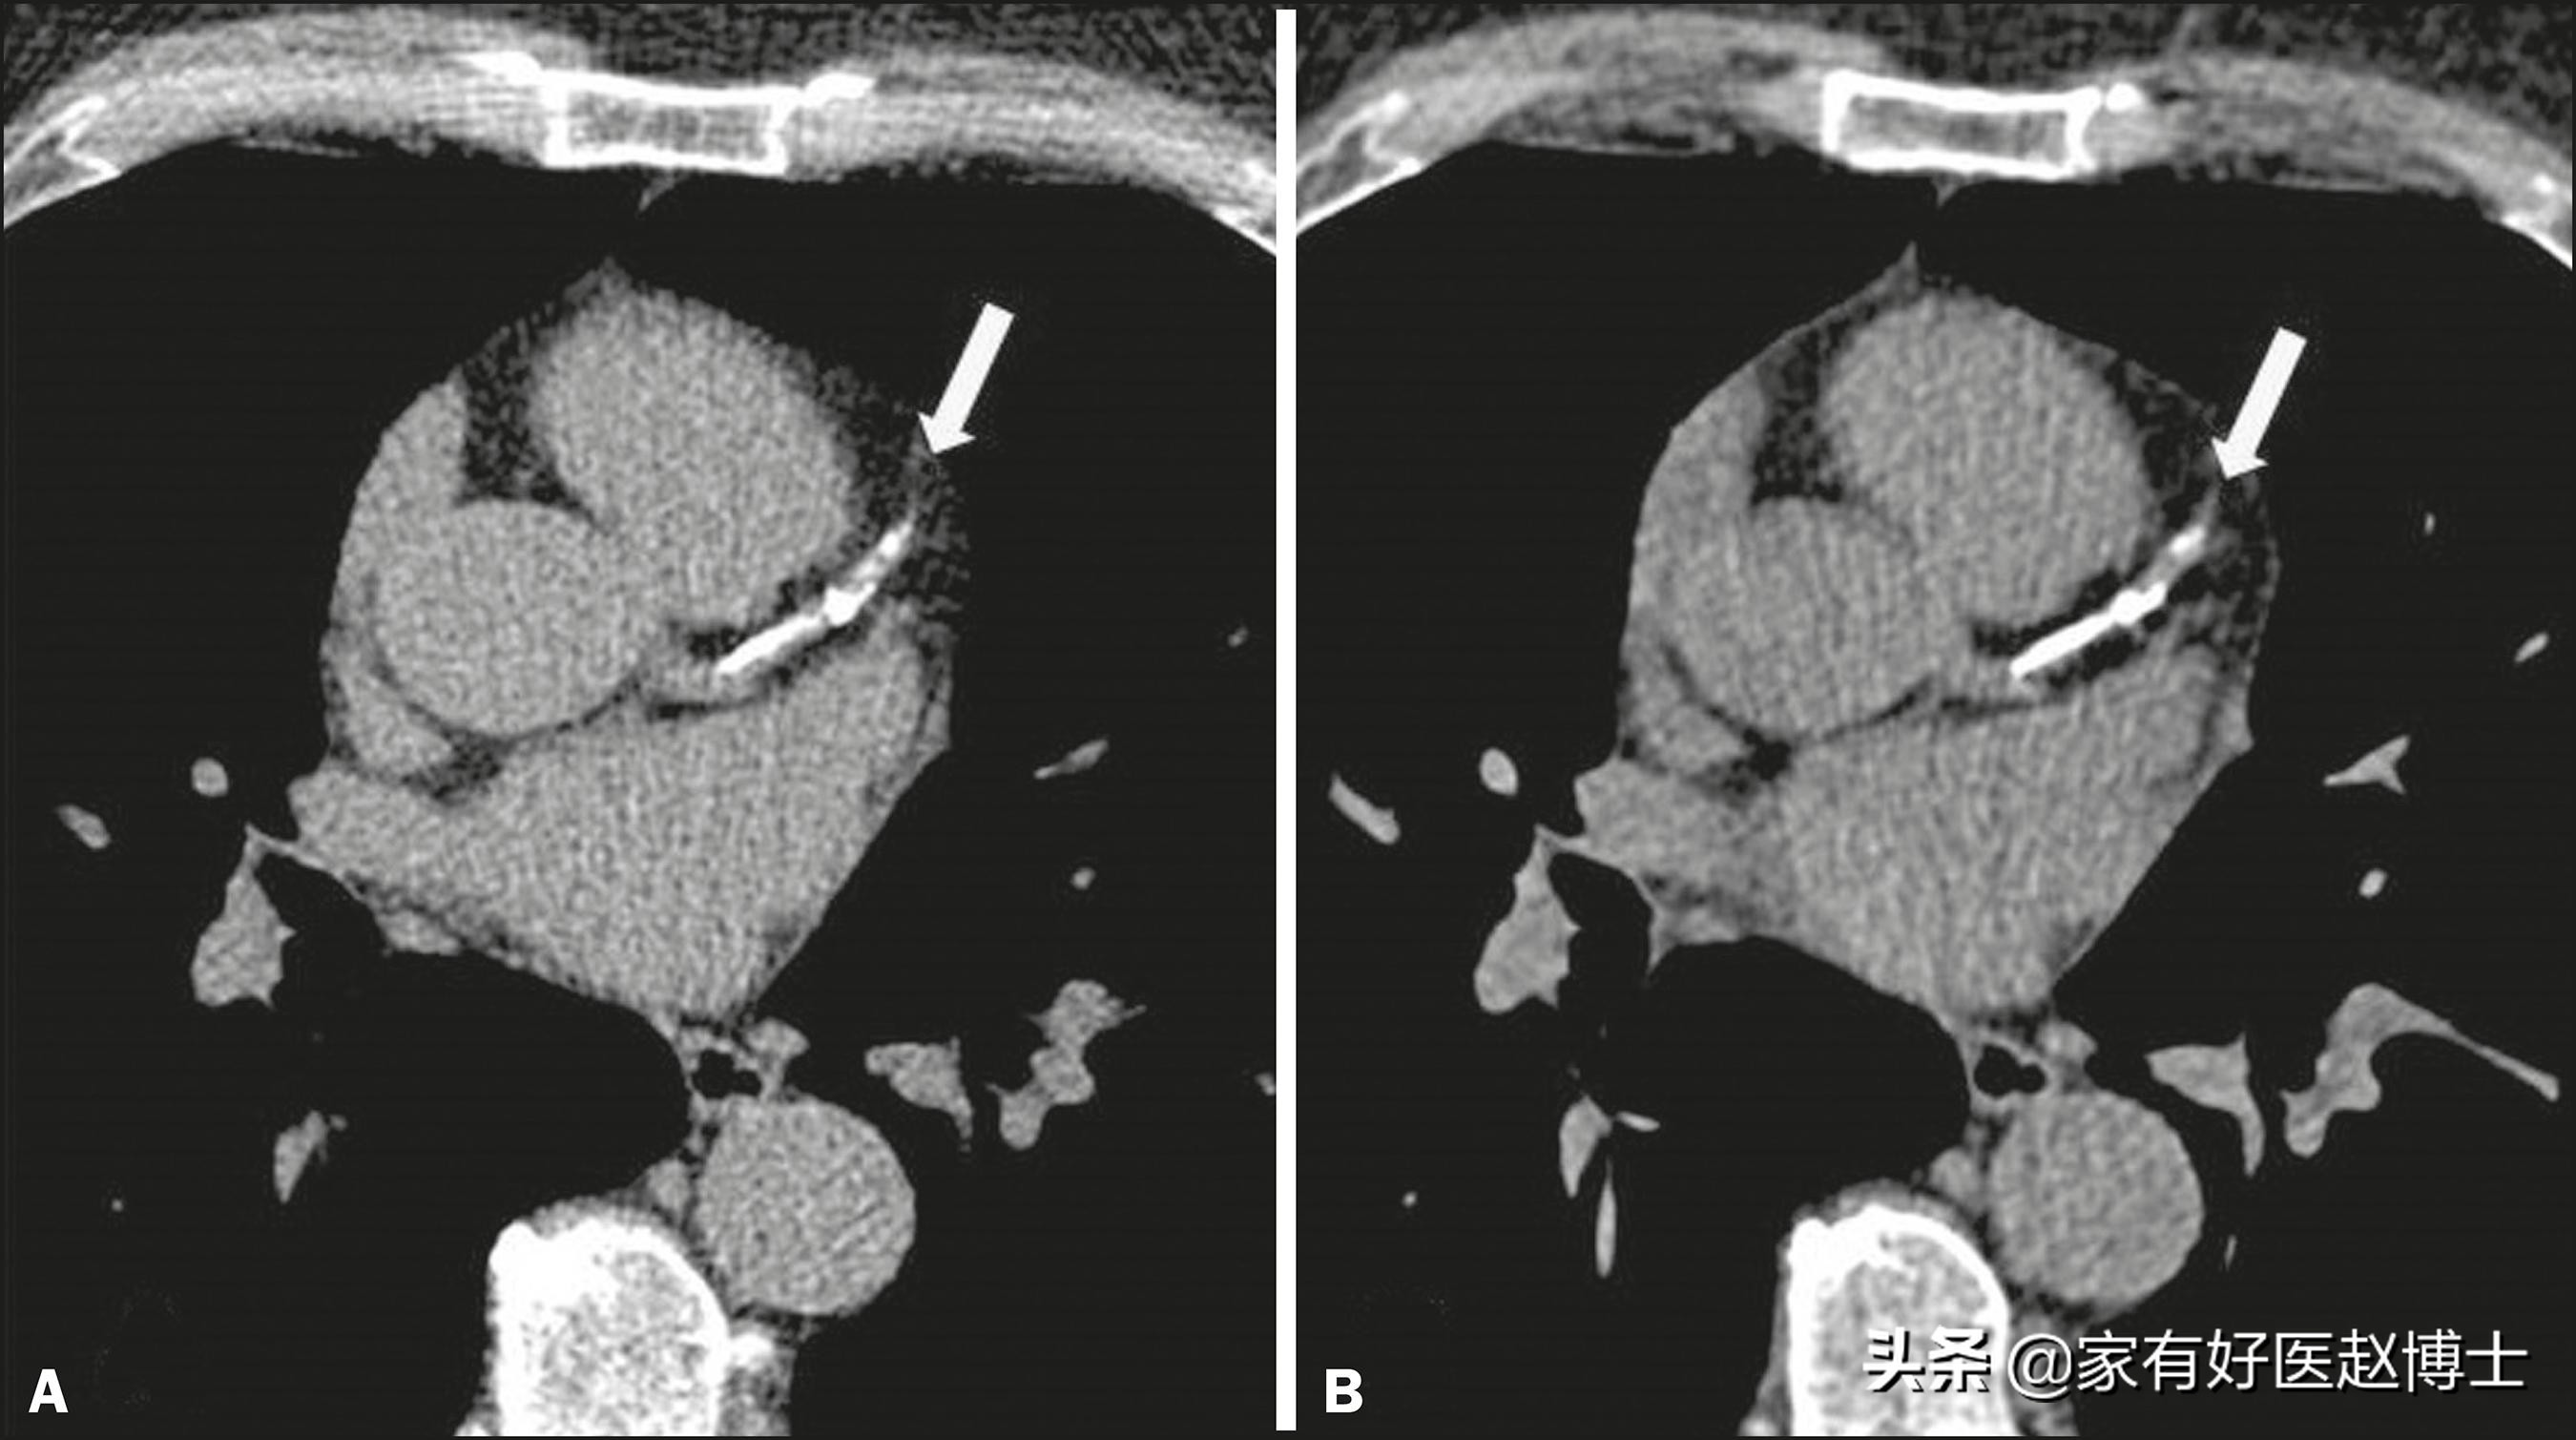

从组织学和影像学的角度,动脉钙化可以为分为两大类:“微钙化”与“大钙化”,它们对于动脉粥样斑块稳定性的影响,是有所不同的。微钙化也叫做“点状钙化”,主要是指钙沉积的颗粒大小不超过2mm的动脉钙化;而大钙化的钙沉积颗粒大小往往超过2mm,≥5mm的连续钙化段被称为“弥漫性钙化”。

点状钙化与弥漫性钙化

研究认为,微钙化往往提示动脉斑块不稳定性风险较高,发生严重心血管事件的概率增加;而大钙化则相反,往往反映动脉粥样斑块的发展处于非活跃期,炎症程度轻微,斑块较为稳定,发生破裂的风险低。